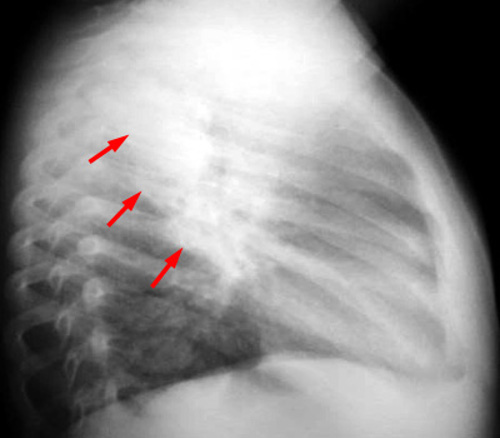

Информация о диссеминированном рассеянном энцефаломиелите